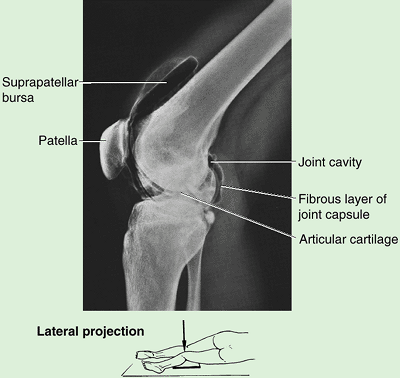

Knee (L. genu) or knee region (L. regio genus). This part/region includes the prominences (condyles) of the distal femur and proximal tibia, the head of the fibula, and the patella (knee cap, which lies anterior to the distal end of the femur) as well as the joints between these bony structures. The posterior part of the knee (L. poples) includes a well-defined, fat-filled hollow, transmitting neurovascular structures, called the popliteal fossa.